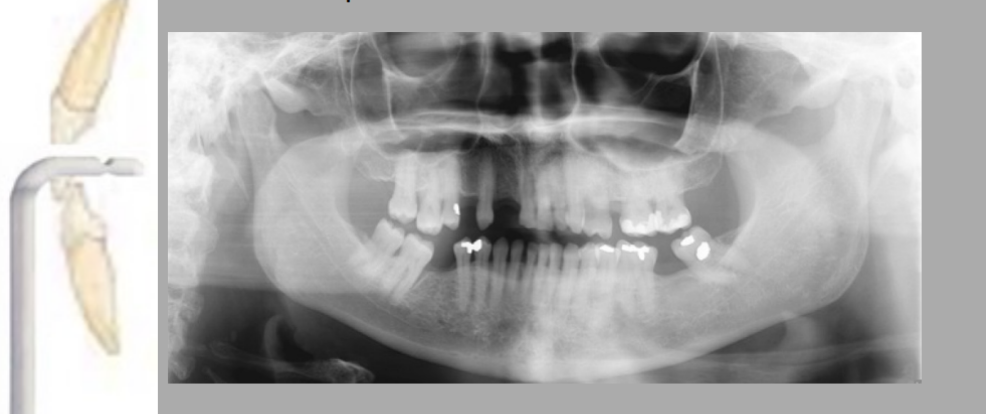

Which error is most significant in the way the patient was positioned?

A. Head is turned too much to right

B. Head too far back

C. Head too far forward

D. Head turned to the right too much